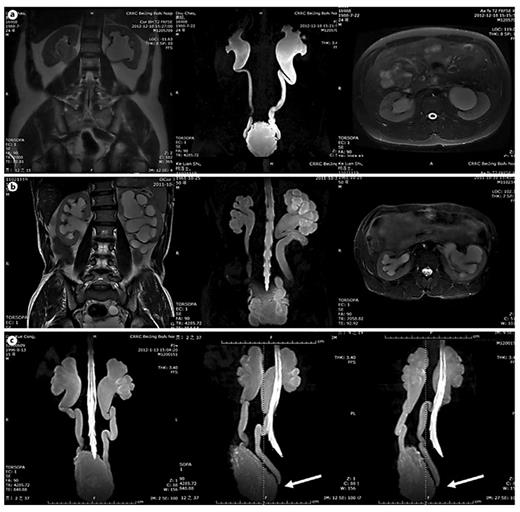

In table 1, LUTD is described according to the Guidelines of the European Association of Urology (EAU) [2] and the terminology of the International Continence Society (ICS) [5]. VUR was graded according to the IRSG, and kidney function was determined by the glomerular filtration rate from isotope renography and the serum level of creatinine. UUTD was graded as follows: grade 0, the central renal complex is closely apposed without UD (fig. 1a); grade 1, slight separation of the central renal complex exists, and the ureter is <7 mm in diameter (fig. 1b); grade 2, the renal pelvis is further dilated, a single or a few calices may be visualized and the ureter is <10 mm in diameter (fig. 1c); grade 3, the renal pelvis is dilated, there are fluid-filled calices throughout the kidney, the renal parenchyma overlying the calices has thinned (renal parenchyma loss <50%), and the ureter is tortuous and <15 mm in diameter (fig. 2a), and grade 4, similar to grade 3, but the renal parenchyma over the calices is thinned (renal parenchyma loss >50%), the ureter is severely tortuous and the ureter is >15 mm in diameter (fig. 2b). For NB patients, detrusor fibrosis and thickening secondary to progressive destruction of the bladder wall often result in ureteral strictures within the bladder wall and distal ureteral obstruction (fig. 2c), which is an important factor in the etiology of UUTD, including HN and UD, and often results in chronic renal failure. Therefore, this new system better discriminates among grade changes in UUT function, can provide objective indicators for UUT function and is an important component of long-term follow-up of conservative and surgical treatment (fig. 3).

MRU UUTD grades 0-2. a Grade 0 UUTD: MRU reveals no separation of the central renal complex of the kidneys and no dilation of the ureters. b Grade 1 UUTD: MRU reveals slight separation of the central renal complex of the kidneys and the ureters are <7 mm in diameter. c Grade 2 UUTD: MRU shows that the renal pelvis of the left kidney is further dilated, a few calices may be visualized and the left ureter is <10 mm in diameter.